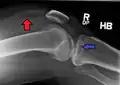

In all injuries to the tibial plateau radiographs (commonly called x-rays) are imperative. Computed tomography scans are not always necessary but are sometimes critical for evaluating degree of fracture and determining a treatment plan that would not be possible with plain radiographs.[5] Magnetic Resonance images are the diagnostic modality of choice when meniscal, ligamentous and soft tissue injuries are suspected.[6][7] CT angiography should be considered if there is alteration of the distal pulses or concern about arterial injury.

Lipohemarthrosis (presence of fat and blood from bone marrow in the joint space after an intraarticular fracture) seen on X-ray in a person with a subtle tibial plateau fracture

Lipohemarthrosis due to a tibial plateau fracture